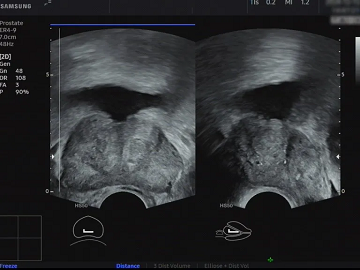

腔内超声(经直肠):深入观察前列腺和精囊腺的发育状态,检查是否有精囊腺缺乏、囊肿、输精管阻塞扩张,为无精子、血精子、弱精子等问题的诊断提供直接的图像依据。